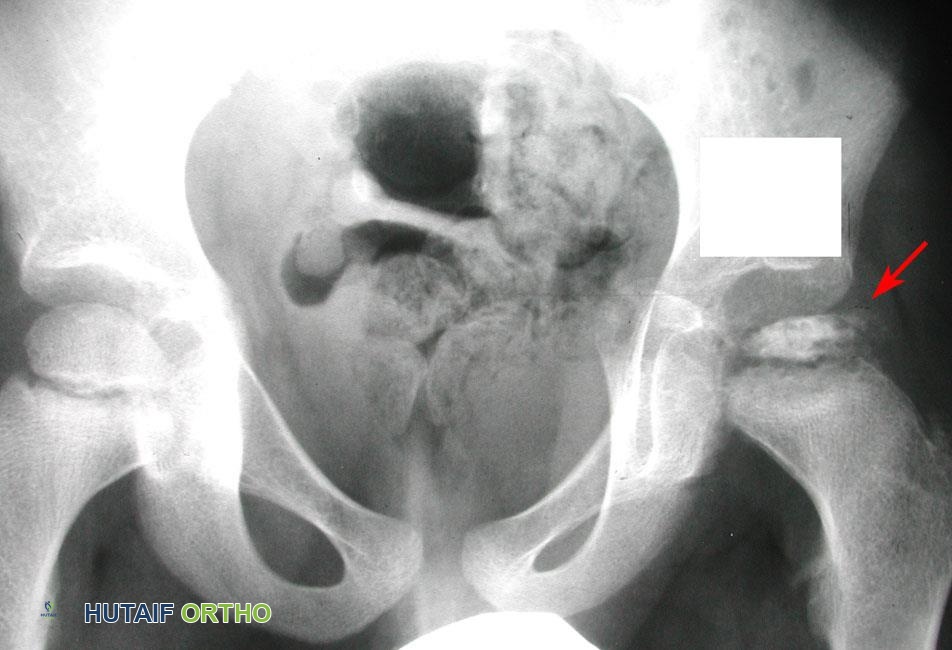

صورة طبية: مرض بيرثيز عند الأطفال: دليل شامل للآباء والعلاج المتطور في صنعاء مع الأستاذ الدكتور محمد هطيف